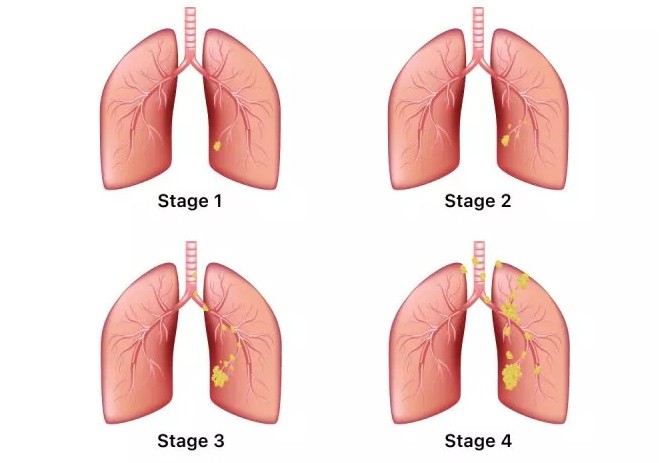

안녕하세요! 오늘은 폐렴의 초기 증상에 대해 알아보려고 합니다. 갑자기 기침이 심해지거나 숨이 차는 등 평소와 다른 호흡의 변화가 있을 때, 그 증상이 단순한 감기인지 아니면 폐렴으로 이어지는 문제인지를 구분하는 것이 중요합니다. 폐렴은 빠르게 진행될 수 있기 때문에, 초기 증상에 대한 인식을 높이는 것이 예방과 치료에 큰 도움이 됩니다.

폐렴은 조기에 치료하면 완치가 가능하지만, 늦으면 합병증이 발생할 수 있으므로 증상이 나타나면 즉시 의료기관을 방문하는 것이 중요합니다.

폐렴의 초기 증상을 잘 알고 있다면, 더 빠르게 적절한 조치를 취할 수 있습니다. 만약 자신이나 주변에 폐렴 의심 증상이 나타난다면, 지체하지 말고 병원을 방문해 꼭 진료를 받으세요. 건강은 무엇보다 중요하니까요! 이번 글이 도움이 되셨기를 바랍니다. 감사합니다.